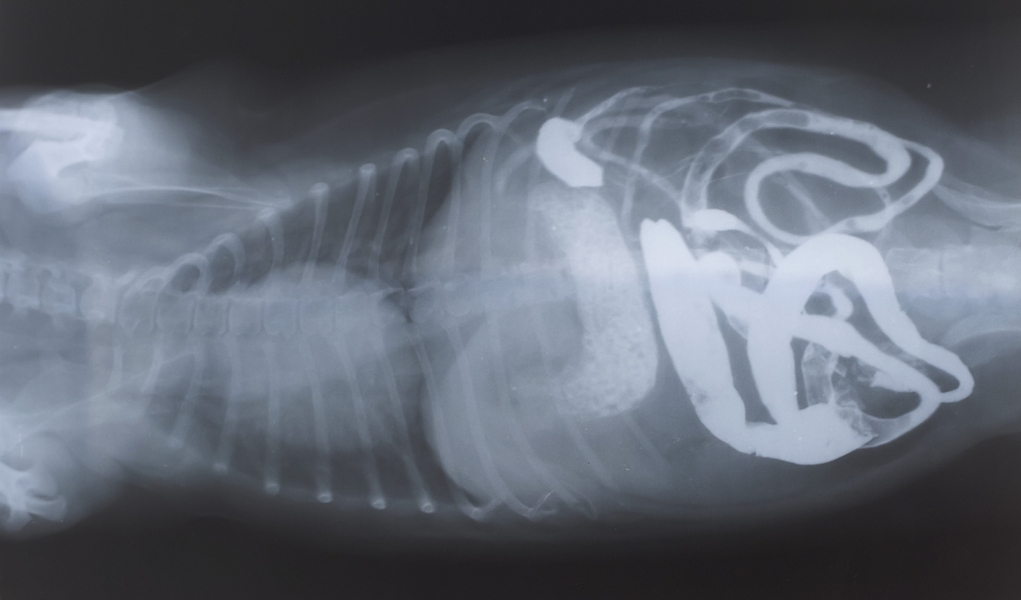

Digestive System Of A Dog, Xray View Photograph by Stocktrek Images Digestive Tract Dog the digestive system absorbs and digests food and eliminates solid wastes from the body and includes the: The system, comprising the mouth, esophagus, stomach, small and large intestines, and colon, works to break down food, extracting essential nutrients. The dog’s digestive system is incredibly complicated which does not make for an easy life. your complete, accurate description of. Digestive Tract Dog.